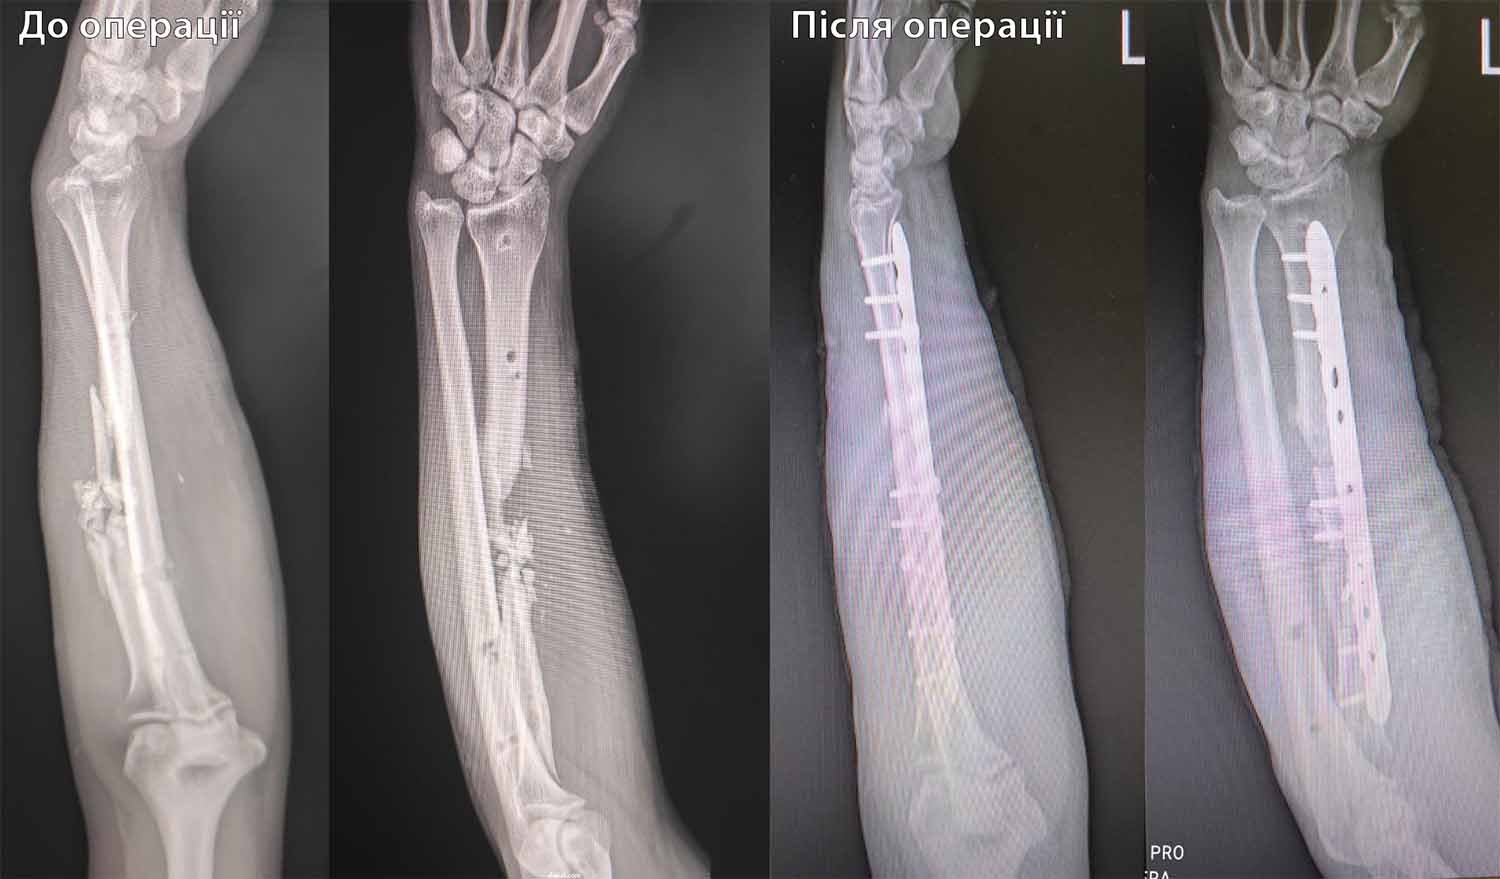

Під час чергового бойового завдання, отримав тяжке, кульове поранення лівого передпліччя, з багатоуламковим переломом променевої кістки та дефектом кісткових та мʼяких тканин. Насправді, я і подумати не міг що рука буде функціонувати, але завдяки професіоналізму лікарів, а саме Досяка Мирослава Ігоровича, він не тільки врятував руку, а і відновив її функції!